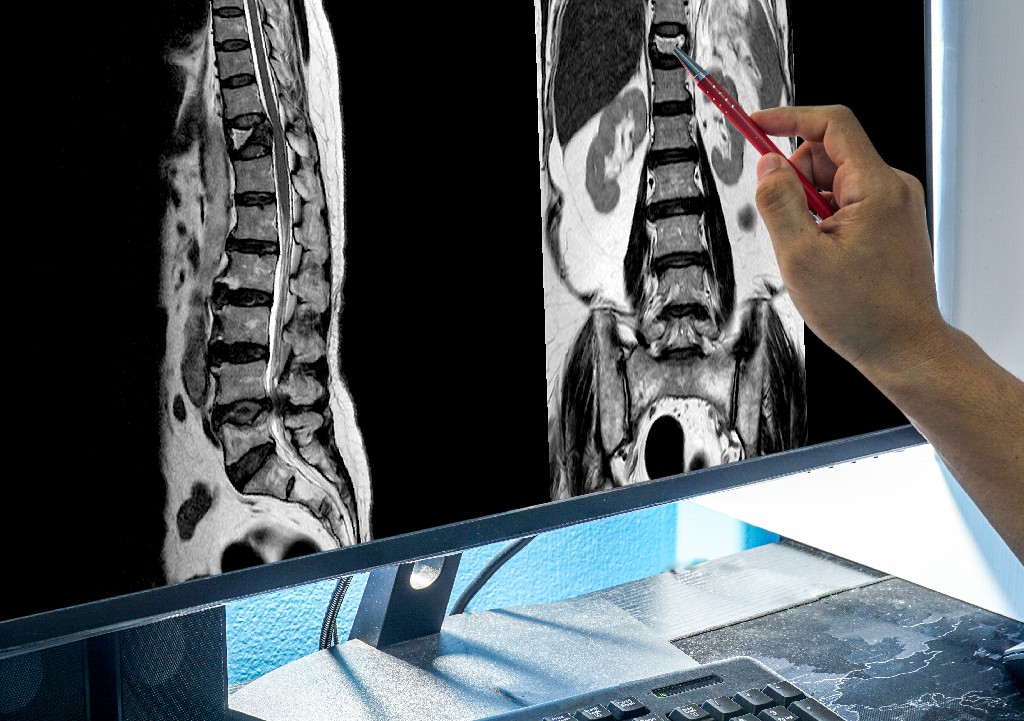

Остеопороз – это состояние, при котором снижается плотность костной ткани, кости становятся слишком тонкими и хрупкими, из-за чего возникает высокая степень риска переломов. В течение жизни у человека костные клетки постоянно обновляются, >>> Подробнее

Основные факты Примерно 1,71 миллиарда человек в мире страдают от нарушений и болезней костно-мышечной системы. Основная доля бремени болезней костно-мышечной системы приходится на люмбаго, от которого страдают 568 миллионов человек в мире. >>> Подробнее